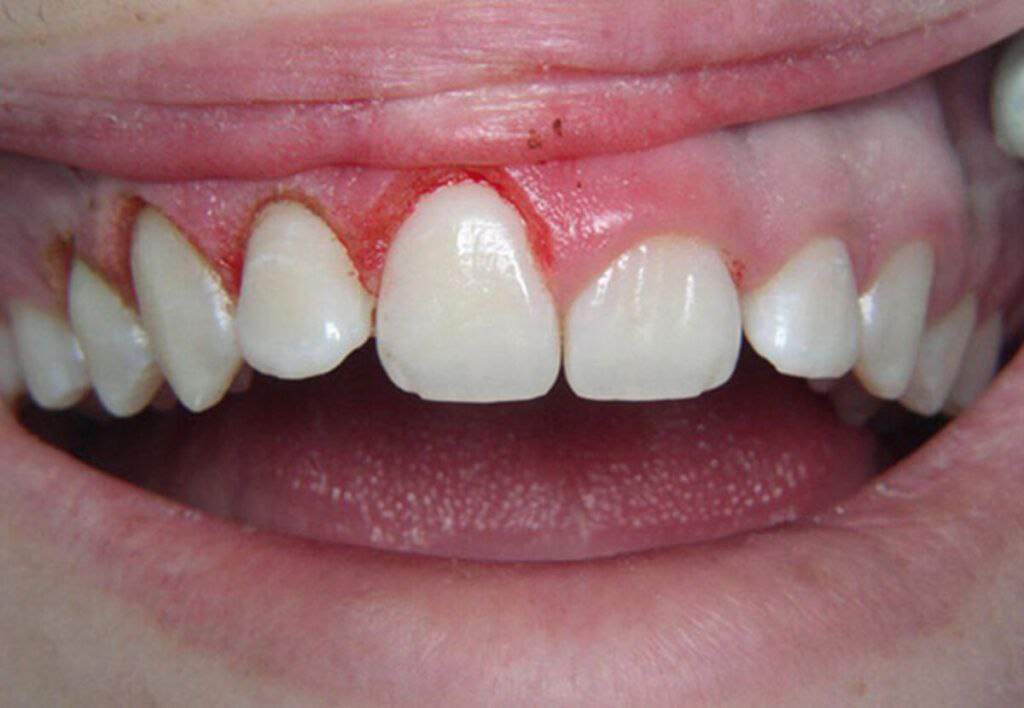

جراحی لثه(افزایش طول تاج)